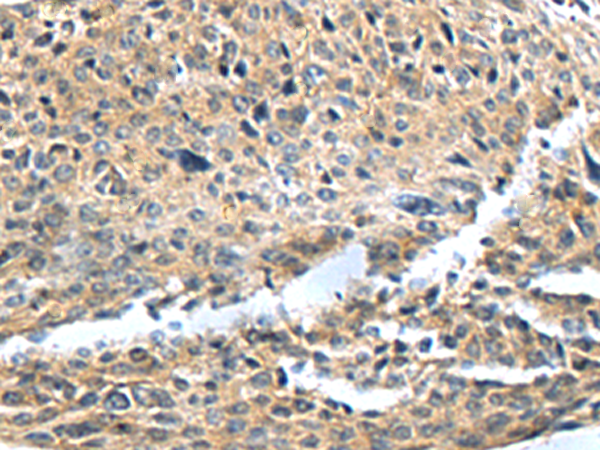

The image is immunohistochemistry of paraffin-embedded Human cervical cancer tissue using P05116(SLC22A12 Antibody) at dilution 1/35. (Original magnification: ×200) |